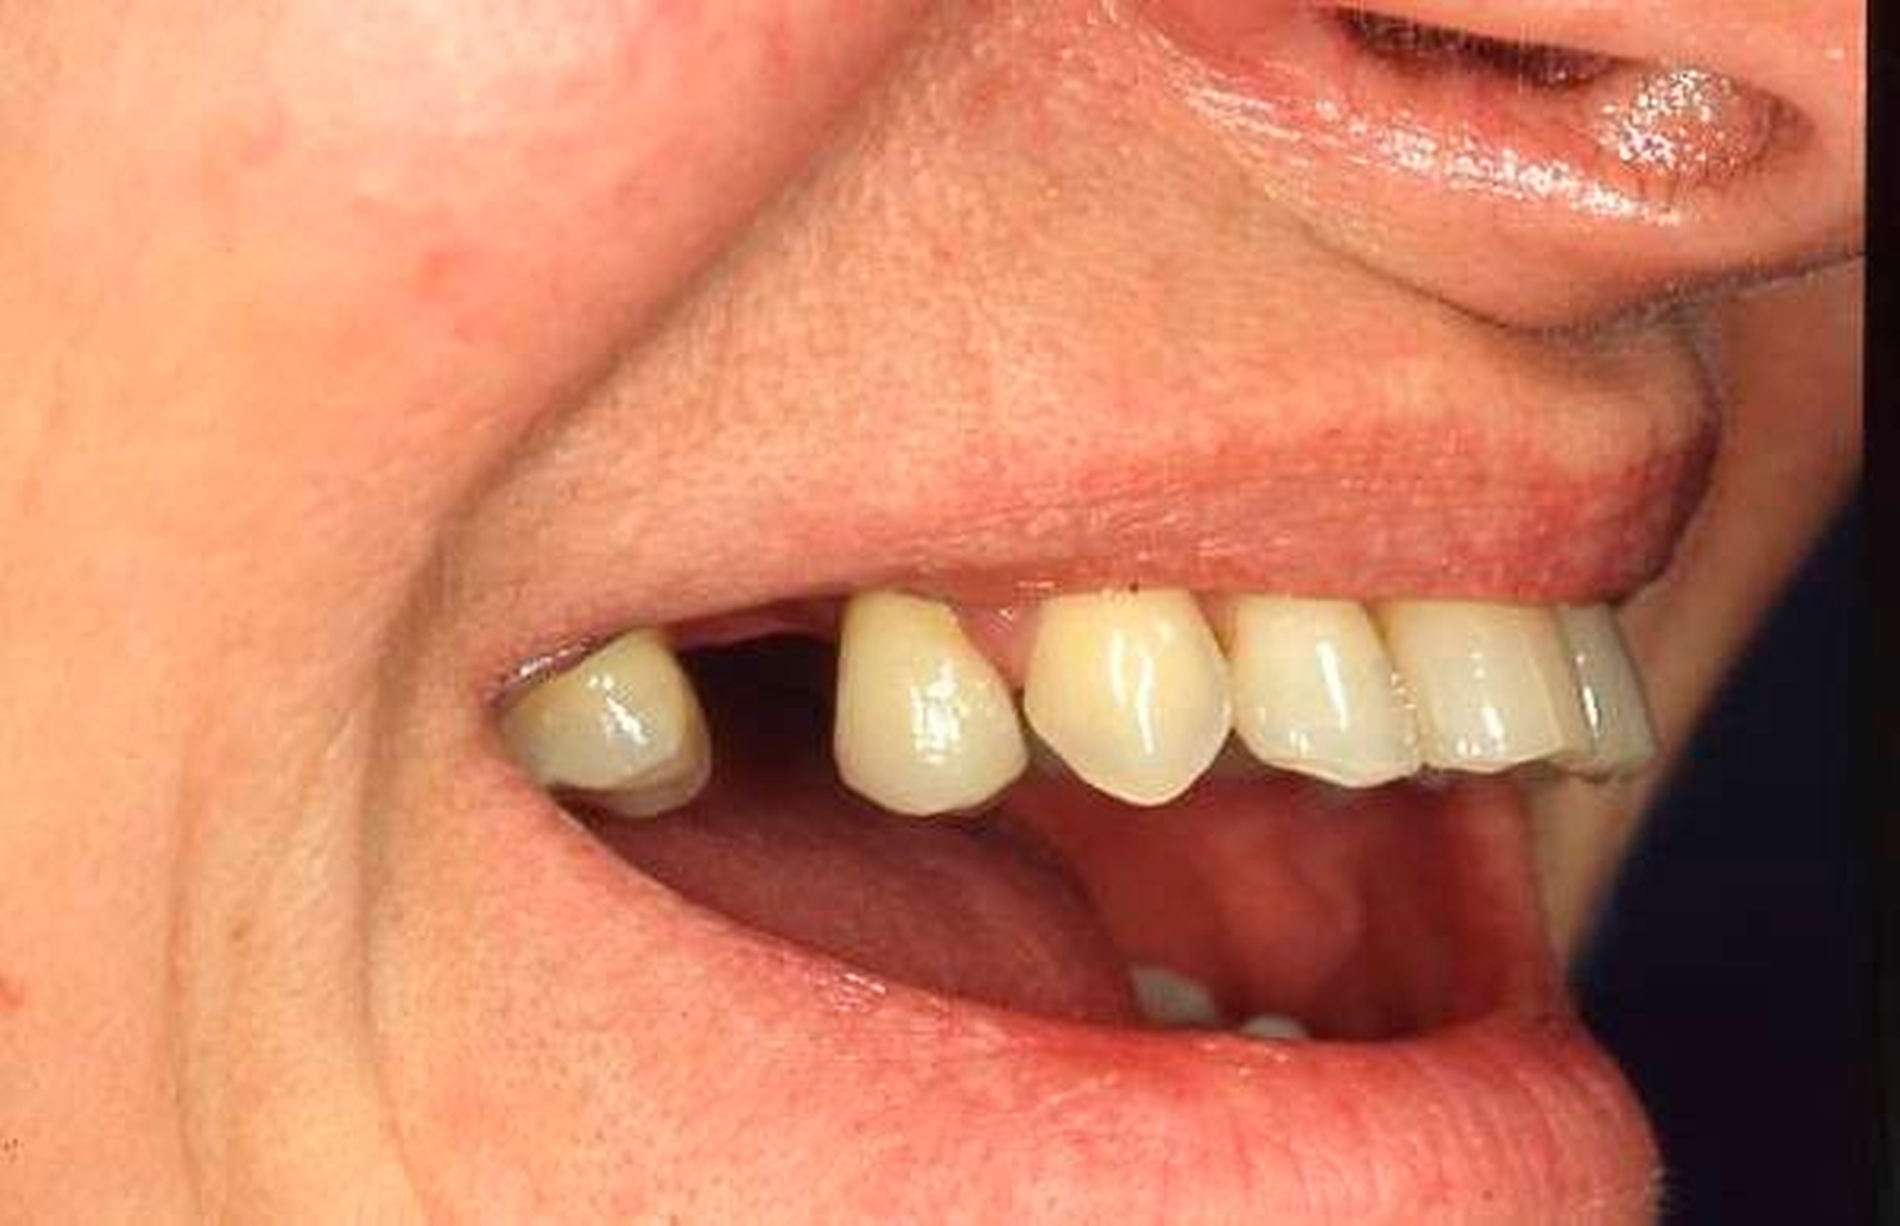

In der Zahnmedizin ist ein Dogma weit verbreitet: „Jede Lücke muss rasch geschlossen werden.“ Tatsächlich gibt es jedoch viele Situationen, in denen es ohne relevante funktionelle und ästhetische Einbußen vertretbar erscheint, eine Lücke zu belassen und regelmäßig zu beobachten (Monitoring). Derzeit erfolgt die Entscheidung „Lücke belassen versus Lücke schließen“ oftmals subjektiv. Sie ist zuweilen weniger von den Patientenvariablen abhängig als von den Schwerpunkten der betreuenden Zahnärzte (Abbildung 4) [Listl et al., 2016]. Ein fachlich fundiertes Vorgehen, das eine Entscheidung unter einer Nutzen-Risiko-Abwägung trifft und ein Monitoring in die Überlegungen einbezieht, kann ebenfalls in die Kategorie der frugalen Interventionen eingeordnet werden. Gleiches gilt für ein Vorgehen im Sinne des Prinzips der verkürzten Zahnreihe, das inzwischen wissenschaftlich gut evaluiert ist [Walter, 2016] und zu dessen Realisierung auch konservierende Maßnahmen beitragen können (Abbildung 5).

Falls ein Lückenschluss nach Gegenüberstellung der Vor- und Nachteile als angemessen angesehen wird, stellt sich die Frage, mit welchen Hilfsmitteln dies erfolgen soll. Derzeit stehen Implantate und klassische Brückenversorgungen im Vordergrund. Es gibt aber auch etliche nicht- oder minimal-invasive Alternativen, die zum Beispiel bei Einzelzahnlücken in Erwägung gezogen werden können. Dazu zählen unter anderem direkte Verfahren wie Zahnverbreiterungen oder -anhänger (Abbildungen 6 und 7) [Staehle, 2009 und 2012; Staehle et al., 2015]. Zurzeit kommen derartige Maßnahmen nur in Einzelfällen in Betracht, es bedarf noch weiterer Evaluationen, um ihr Indikationsspektrum genauer abgrenzen zu können. Es zeichnet sich aber jetzt schon ab, dass sie ein gewisses Potenzial als frugale Interventionen besitzen. Auch wenn momentan vielfach Implantate favorisiert werden, erscheint es dennoch sinnvoll, wenn die Zahnärzteschaft auch diverse Implantat-Alternativen vorhalten kann. Ungeklärte Probleme periimplantärer Entzündungen [Chrcanovic et al., 2016] und die zu erwartende Diskussion über Beziehungen zwischen periimplantären Entzündungen und der Allgemeingesundheit lassen es als sinnvoll erscheinen, solchen Fragen intensiver als bisher nachzugehen. Bislang wird zwar nur über Einflüsse der Allgemeingesundheit auf den Erfolg beziehungsweise Misserfolg von Implantaten diskutiert. Es ist aber nicht auszuschließen, dass man künftig die Fragestellung in umgekehrter Richtung dahingehend erweitert, inwieweit Implantate ihrerseits nicht nur positiven, sondern auch negativen Einfluss auf die Allgemeingesundheit nehmen können.